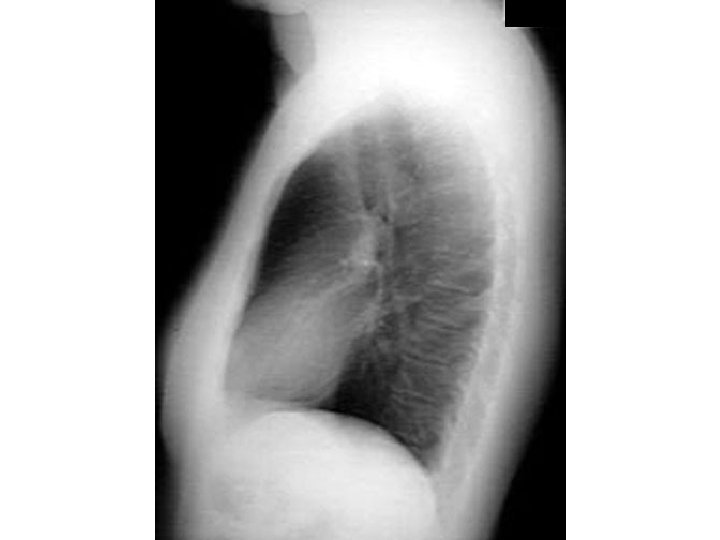

Emphysema Flat diaphragm

Dark lungs AP diameter Low flat diaphragms Vertical heart Retrosternal air Infracardiac air Avascularity

Dark lungs AP diameter Low flat diaphragms Vertical heart Retrosternal air Infracardiac air Avascularity Blebs Emphysema